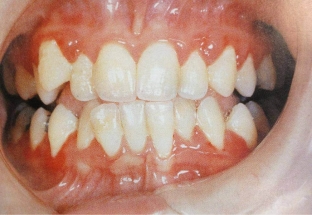

Гіпертрофічний гінгівіт проявляється відчуттям печіння, кровоточивістю ясен та хворобливістю під час процедури чищення зубів. Про зовнішній вигляд ясен при гінгівіті читайте на estet-portal.com. Десна має яскраво – червоний колір визначається гіпертрофія міжзубних проміжків. При огляді ясенові сосочки збільшені у розмірі, набряклі, визначається гіперемія з синюшним відтінком. Десневі сосочки мають глянсовий блиск. Часто формуються ясенні кишені, що містять детрит. Зубодеснева сполука при гіпертрофічному гінгівіті не порушена.

Фіброзний гінгівіт проявляється скаргами пацієнта на збільшення ясен, їх виражену щільність та зіпсований естетичний вигляд. Така ясна може створювати дискомфортні відчуття при пережовуванні їжі. При цьому вона має блідо – рожевий колір та нерівну поверхню. Під час огляду виявляються підясенні відкладення.